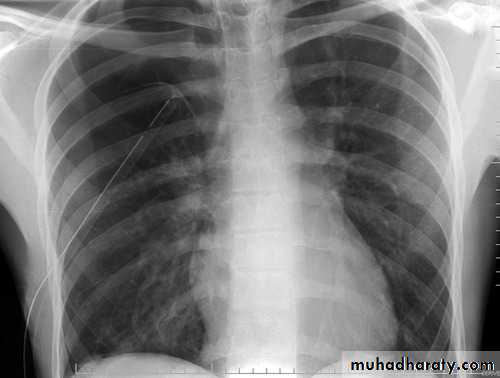

Pneumothorax

!! pneumothorax

Area of hypertranslucensy (pneumothorax)